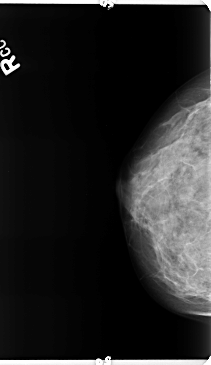

B_3359_1.RIGHT_CC

RIGHT_CC LINES 4736 PIXELS_PER_LINE 2736 BITS_PER_PIXEL 12 RESOLUTION 50 NON_OVERLAY